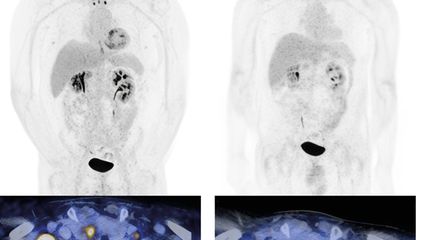

L’étude a randomisé les patient·es éligibles à la transplantation dans trois bras thérapeutiques: immunochimiothérapie d’induction suivie d’une autogreffe de cellules souches; immunochimiothérapie+ibrutinib suivie d’une ASCT et de deux ans de traitement d’entretien par ibrutinib; ou immunochimiothérapie+ibrutinib sans ASCT, suivie de deux ans d’entretien par ibrutinib. Au moment de la conception de l’étude TRIANGLE, le traitement d’entretien par rituximab ne constituait pas encore un standard; il ne faisait donc pas partie du protocole et a été administré, selon les pratiques nationales, à la majorité des patient·es dans les trois bras, avec une fréquence comparable. Dans les deux bras de traitement contenant de l’ibrutinib, une amélioration statistiquement significative et cliniquement pertinente de la survie sans échec (FFS) et de la survie globale (OS) a été observée par rapport à l’immunochimiothérapie standard suivie d’une ASCT: le taux de FFS à 3 ans était de 88% et 86%, respectivement, contre 72%, et le taux de survie globale à 3 ans de 91% et 92%, respectivement, contre 86% (Fig.1).4

Aucune supériorité n’a pu être démontrée pour l’ancien standard comprenant l’ASCT (sans ibrutinib) par rapport au bras ibrutinib sans ASCT.4

Ces résultats ont conduit à considérer l’ajout de l’ibrutinib à l’immunochimiothérapie d’induction, suivi d’un entretien par ibrutinib et rituximab, comme le nouveau standard chez les patient·es plus jeunes atteint·es de MCL (avec autorisation correspondante de l’ibrutinib en première ligne dans l’UE). Une chimiothérapie à haute dose avec ASCT ne fait donc plus partie du traitement standard chez les patient·es recevant l’ibrutinib en induction et en entretien.